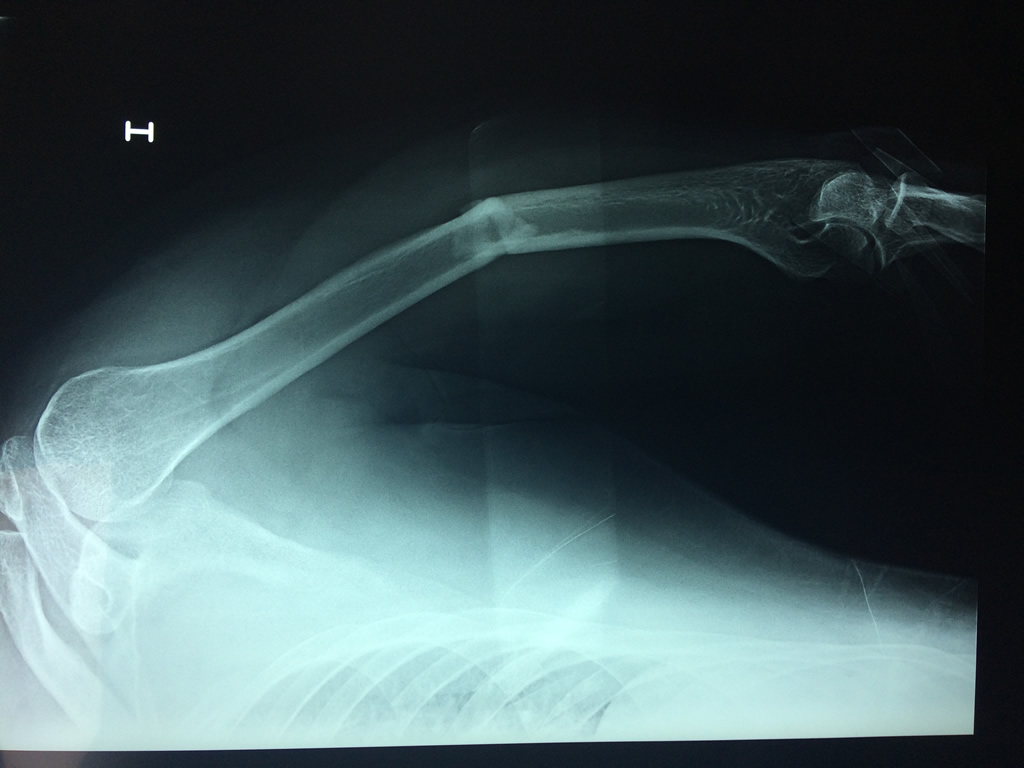

Cirugía de Fémur - Húmero

El Húmero (en latín, humerus) es el hueso más largo de las extremidades superiores en el ser humano. Forma parte del esqueleto apendicular superior y está ubicado en la región del brazo. ... El extremo proximal del húmero tiene la cabeza, cuellos quirúrgico y anatómico y tubérculos mayor y menor.